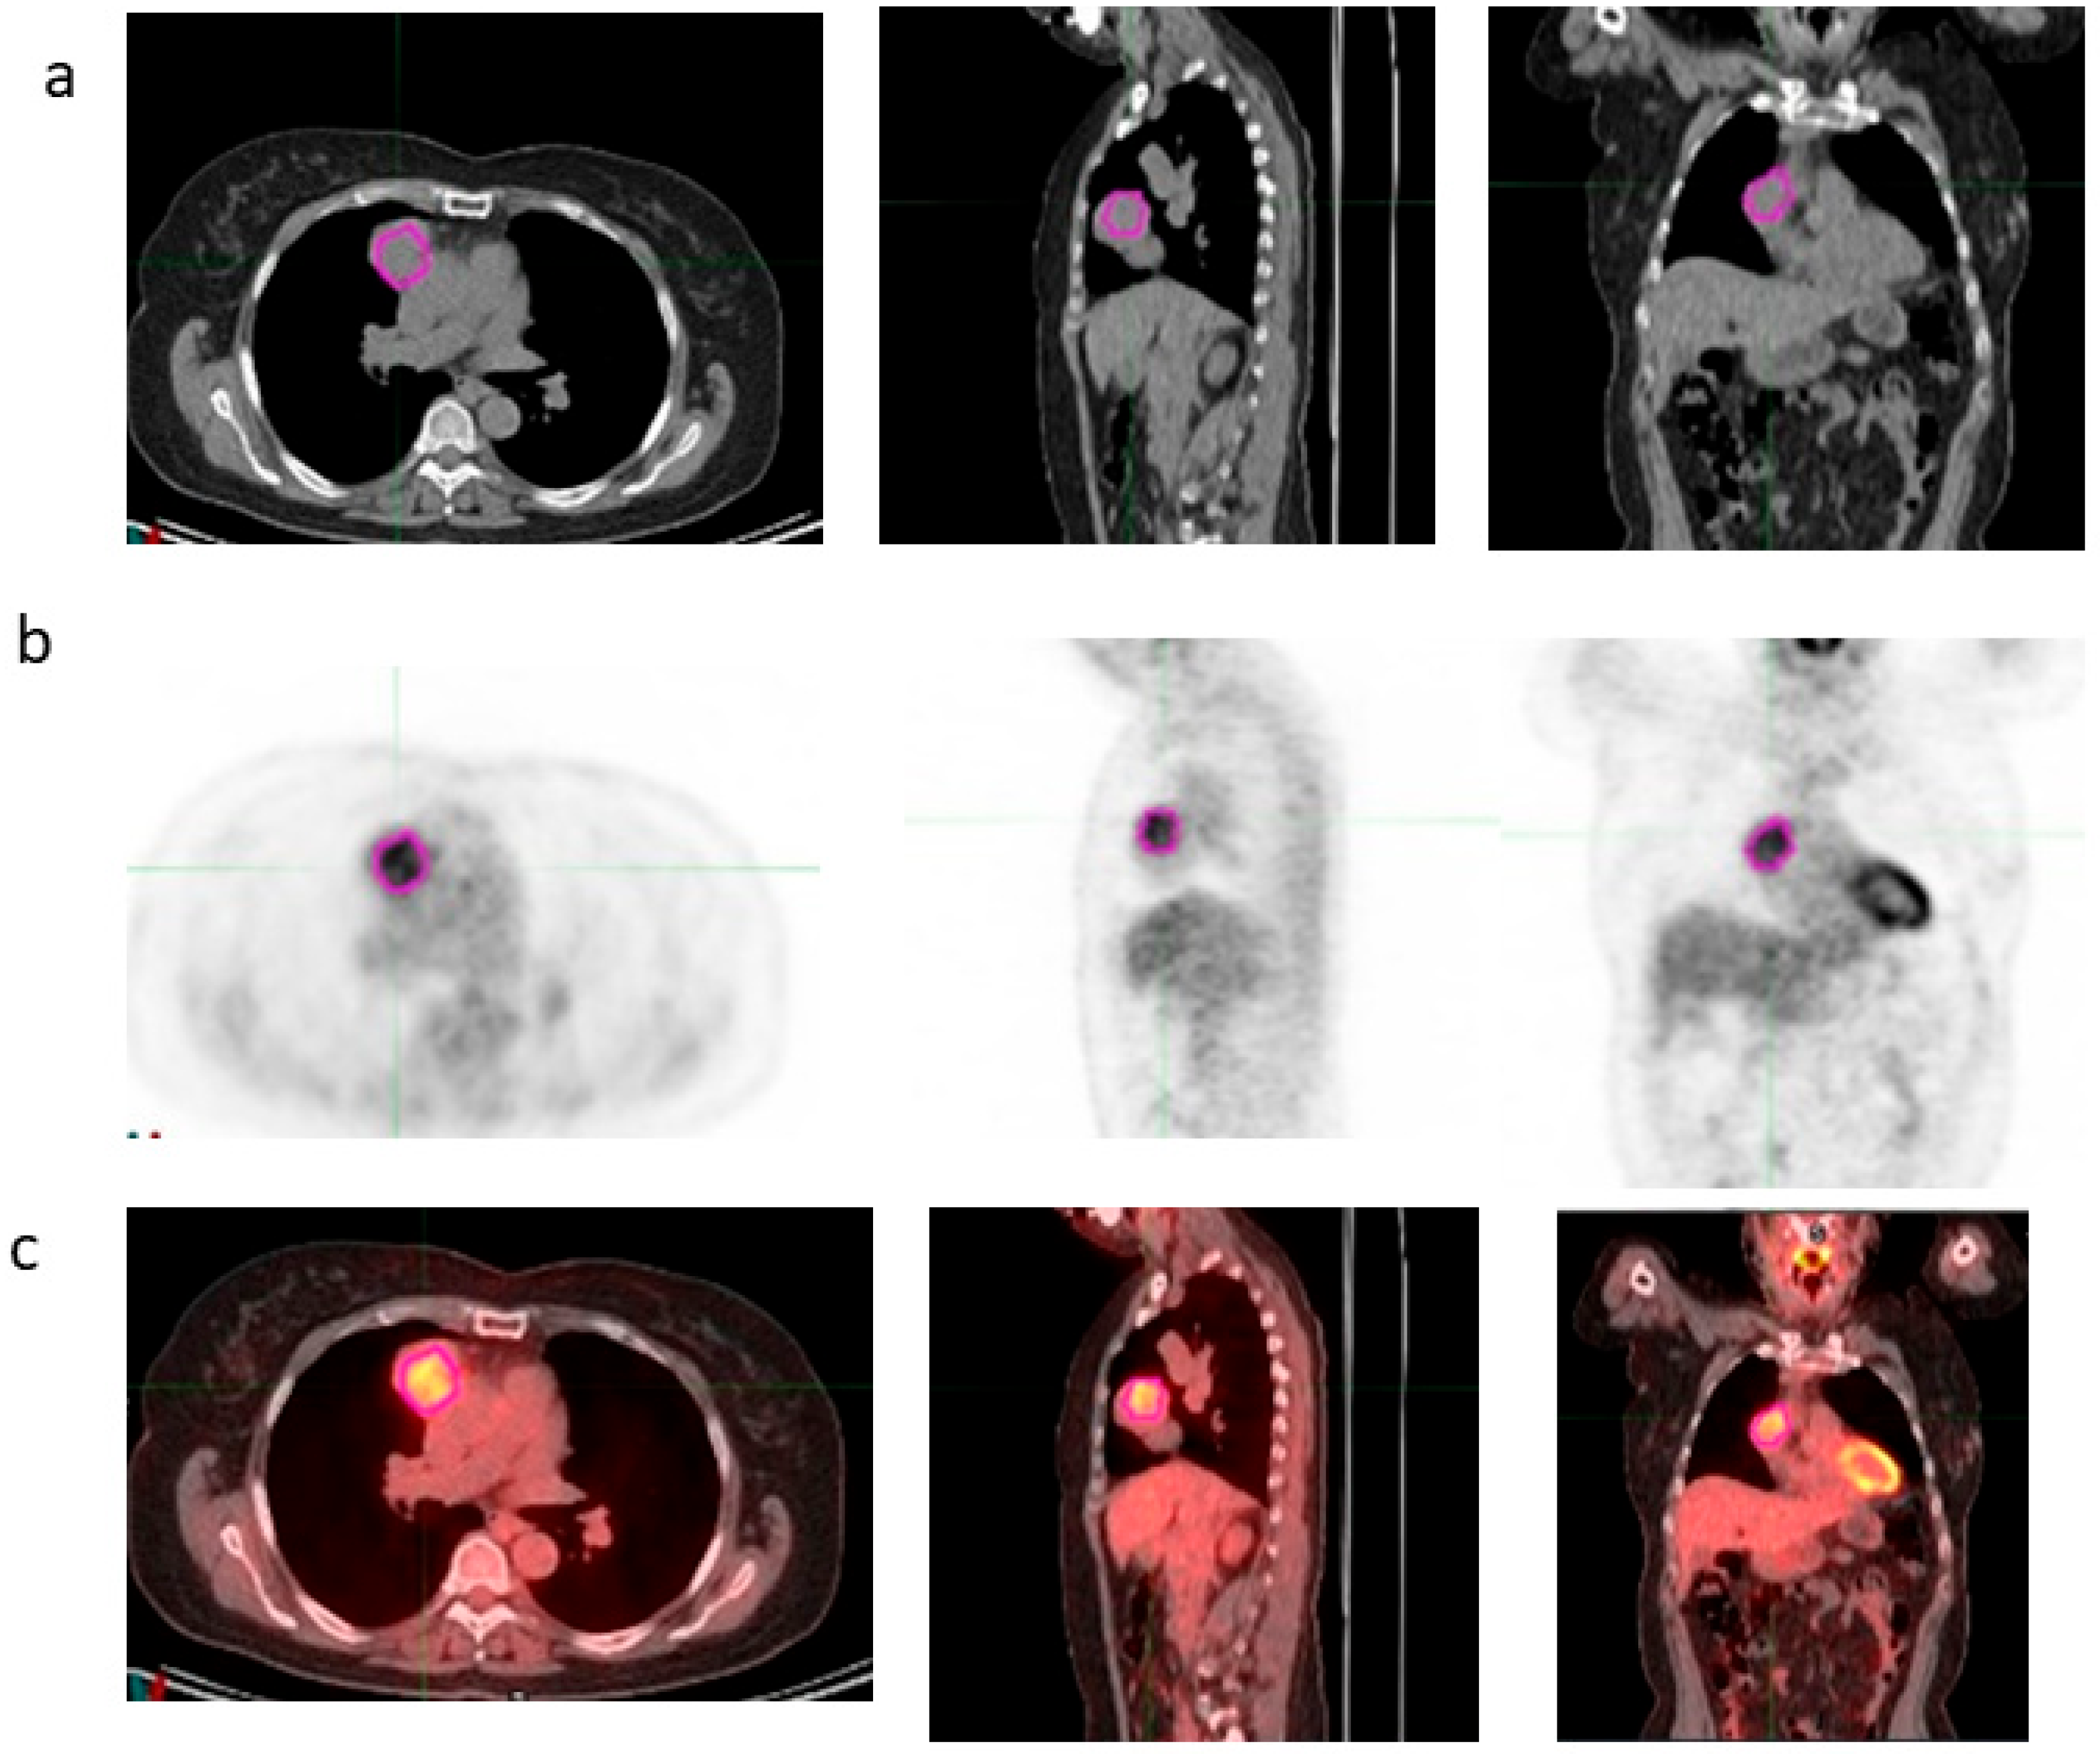

VOI segmentations of the thymic lesions were manually performed on [18F]FDG PET/CT images by two expert nuclear medicine physicians on MIM maestro version 7.3.2 (MIM Software, Inc., Cleveland, OH, USA), as shown in Figure 1. Any discrepancies were resolved by consensus.

Figure 1.

Manual segmentation of the VOI on transaxial CT (a), PET (b) and fused (c) images around the area of thymus using MiM Maestro software version 7.3.2.